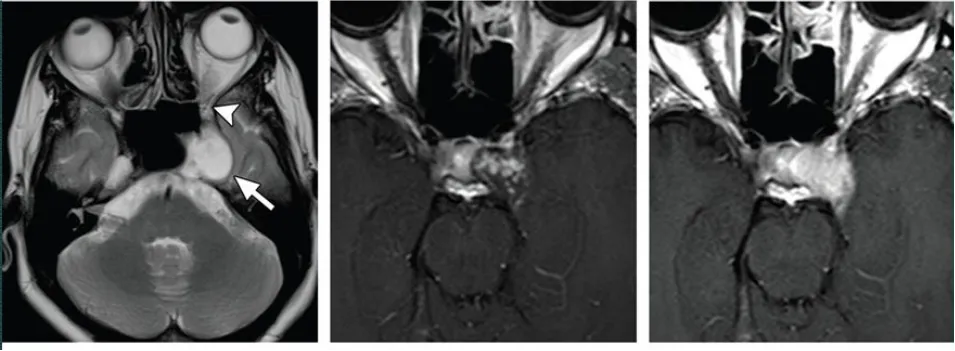

典型病例影像学表现

海绵状神经鞘瘤,瘤内可见囊性变,实性部分强化明显

海绵窦血管瘤,T2加权像呈高信号,累及左侧Meckel腔